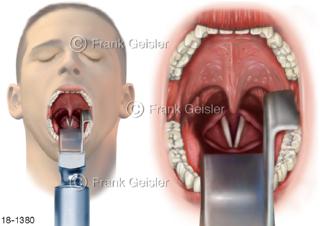

18-1380 Notfall Laryngoskopie, Kehlkopfspigelung Larynx Kehlkopf